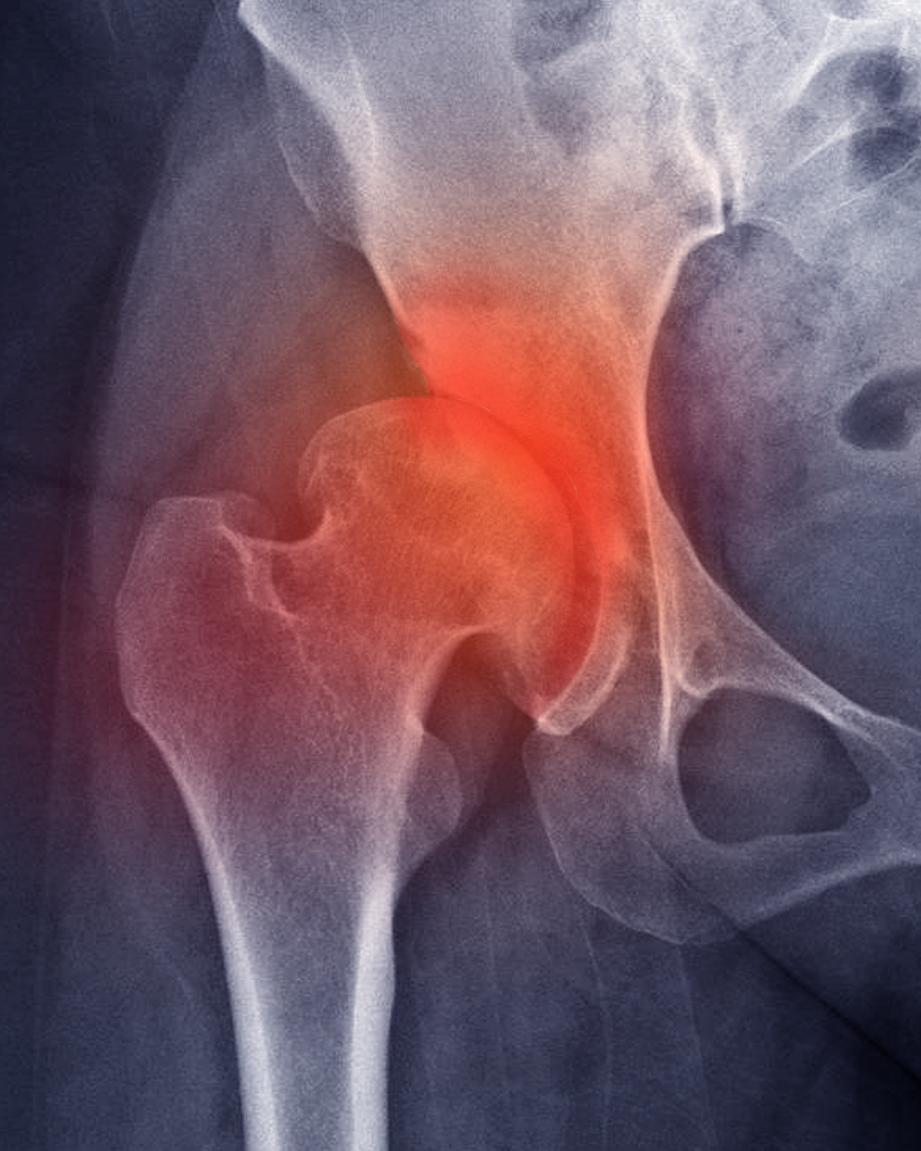

Das Hüftgelenk ist ein Kugelgelenk, bestehend aus dem Hüftkopf des Oberschenkelknochens und der Hüftpfanne des Beckens. Die Gelenkflächen sind mit einer glatten, belastbaren Knorpelschicht überzogen, die eine reibungsarme Bewegung ermöglicht und als Stoßdämpfer dient.

Die Hüftarthrose (Coxarthrose) ist eine degenerative Erkrankung, bei der es zu einem fortschreitenden Abbau des Gelenkknorpels kommt. Durch den Knorpelverlust reiben die Knochen zunehmend aufeinander, was Schmerzen, Entzündungen und Bewegungseinschränkungen verursacht.